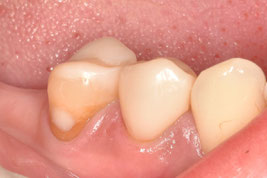

1回法で根管治療を終わらせてデンタルを撮影したところ、目を疑う光景がありました。

「6番の近心根がほぼそのまま残根しているぞ!…どうしよう」

根尖だけ若干残るのなら分かります。しかし、近心根がまるごと残っているのです。

患者さんに残根について説明し、限られたアポイントの中で、なんとか抜歯できました。